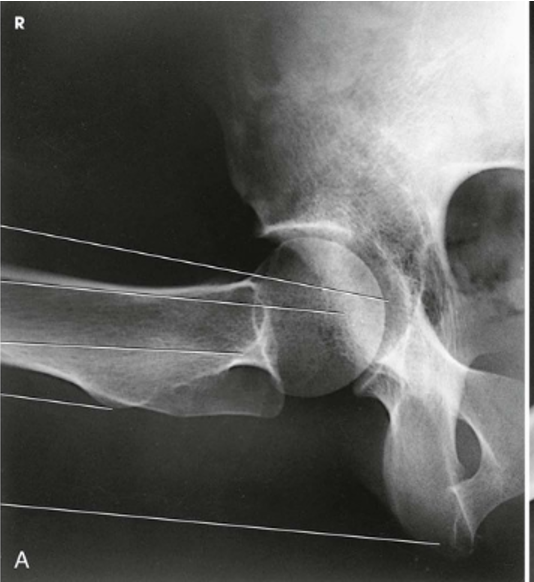

The bilateral image shows an AP oblique projection of the femoral heads, necks, and trochanteric areas onto one radiograph for comparison

AP Oblique Projection; Proximal Femora and Femoral Necks; Modified Cleaves Method